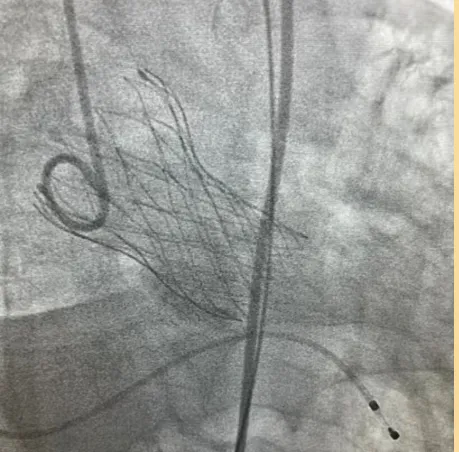

起搏与电生理

我院心脏电生理团队以硬核实力为豫北房颤患者带来多元优质治疗方案常规开展左束支区域精准起搏及无导线起搏器植入。独立完成CardiPulse® PFA联合SeaLA™左心耳封堵一站式手术,开展冷冻球囊消融术治疗房颤,受邀参加全国电生理手术直播,展现了优秀的手术操作技能